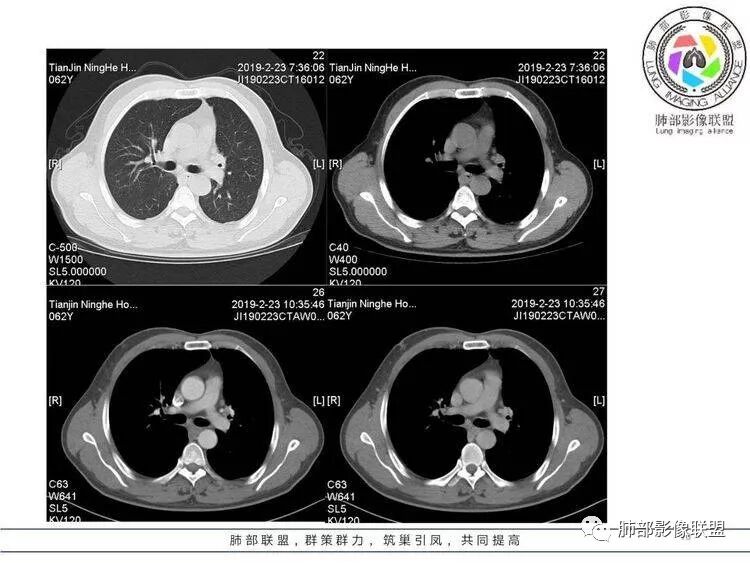

像雾像雨又像风,到底是什么?等你来判断。

病例资料

王秀仙:左肺上叶肿块,边缘平直收缩,周围可见长索条,轻度强化,密度不均可见低密度坏死,考虑结核。鉴别腺癌。Yiren  Sishui(厶水伊人):晨读:左肺上叶肿块,近胸膜侧光滑,提示符合淋巴回流病变,周围条索,符合肉芽肿性病变,环形强化,中心坏死,考虑结核可能luys:左肺上叶病变,沿支气管分布,边缘平直收缩,周围见长索条,轻度强化,伴边界可见低密度坏死灶。考虑特殊感染。灶内支气管中断,临床以咯血就诊,鉴别肿瘤。博麟:左上胸廓稍缩小,长条索病灶,冠状位似见支气管截断,坏死边界似乎欠清,猜个纤维条索基础上合并瘢痕癌红日东升:晨读:左上叶结块,前缘有粗大索条向前延伸,邻近前联合线明显左移,提示收缩明显。结块边缘平直、收缩;增强结块及索条明显强化,内血管走行自然,坏死灶周围似见三层结构;考虑炎性病变。wonderful:肿块实性边缘光滑  考虑良性病变 合并咯血 。结核或曲霉玫:左肺上叶不规则形软组织密度肿块影,边界清晰,期内密度不均匀,可见坏死,病灶向前呈条索状延伸,矢状位病灶形态欠规整,似有血管中断,考虑恶性病变可能,待除外结核?张帅:左肺上叶病变,病变周围平直,长毛刺,病灶内可见低密度区及支气管征,矢状位提示前段阻塞,病灶内气管不规则扩张,病灶周围有卫星灶,考虑良性病变:结核?我心飞翔:病灶边缘平直,中央可见坏死,周围磨玻璃边界欠清,考虑炎性病变张延军:左肺上叶尖后段肿块,边缘以平直为主,局部膨隆,内见片状坏死区,边界欠清,相应尖后段支气管闭塞,考虑占位并不张,腺癌?建议抗炎治疗后复查丽:左肺上叶病变,边缘平直,并可见长索条,增强后密度不均,可见坏死,首先考虑结核,但重建后支气管走形欠连续,似有截断,恶性待排毛勤香:左肺上叶病灶,边缘平直为主,周围索片影,增强强化不均匀,内有坏死,重建支气管走行欠规则,似有截断,老年男性,需排除恶性(鳞癌?)并阻塞性肺炎可能王萍:左肺上叶团片,大部分边缘平直、凹陷,周围见少许条片模糊影,增强内见坏死区,余区域较均质,其内支气管部分通畅,部分变窄。咯血病史,无发热,考虑肉芽肿性炎可能性大,结核或放线菌等,肿瘤待排THINKER:左上叶,占位,围绕尖后段支气管,U型凹丶平直,长索条,有轻强化及低密度,考虑良性的,首选OP,老年不发热丶咯血,鉴鳞癌、TB飞鹰行动:左肺病灶,有明显的收缩表现,增强后病灶内部可见低密度无强化区,病灶内支气管轻度扩张呈串珠状改变,支持炎性病变,结核可能性大。杨泽锋:支持炎性病变伴小脓腔形成,但不支持结核,因为病灶内可以可见血管影THINKER:问一下各位老师:这个给的强化,是肺动末期丶主动脉未期`延迟期?大雄:老年男性,左肺上叶前段条片状实变影伴周围长条索,境界清晰,边缘部分锐利光滑、部分毛糙,增强可见中央局部坏死,周围无强化区轻中度均匀强化,无钙化,无明显卫星灶,无胸膜明显牵拉凹陷。病灶整体收缩力有,张力不明显,肿瘤概率小。临床无明显急性感染症状,倾向于慢性增生性炎症,累及段支气管,引起了咯血。结核多见,但慢性结核肉芽肿一般强化没这么明显。OP不除外。老年男性如果有长期吸烟史,鳞癌不能完全排除,鳞癌的坏死强化都符合,鳞癌收缩力也不强,形态更是变化无常左手:老年男性,咯血,左肺上叶长条样结节,边缘见牵拉影,支气管堵塞,病灶内见坏死,坏死边缘偏清,考虑鳞癌,鉴别结核宇宙星空:支持恶性。鳞癌可能性大。支气管截断及空泡征

Shelia:考虑机化性肺炎伴小脓肿形成?炎性肌纤维母细胞瘤?鉴别癌食客:左肺上叶病灶,边缘平直,周围条片影,增强内见坏死区,内支气管部分通畅,咯血病史,无发热,考虑结核,肿瘤不除外。管洪林:左肺上叶尖后段病变,整体边缘平直,部分稍收缩,临近长索条影,胸膜缘可见轻度牵拉,增强后整体强化明显,其内可见低密度类圆形坏死区,边界清,首先考虑op并小脓肿形成,但部分层面显示小支气管受阻,是否层面原因?管洪林:若是支气管阻塞,鳞癌作为鉴别雪上一枝蒿(陈显静):他这个动脉期是不是不是很明显啊,觉得跟静脉期差不多,强化值也不好分辨?徐超:左肺上叶实变,边缘平直,周围无磨玻璃及卫星灶,病灶内坏死,强化后边界清楚,无壁结节,余病灶轻中度均匀强化(对比肌肉),增强后血管显影清楚自然,未见破坏边缘毛糙,血管旁条形无强化区(粘液?)整体符合炎性特点,炎性假瘤或op可能,伴小脓肿;结核放后面待排(结核病灶内血管完好,边缘清楚,且强化近中度,不是很合理,肉芽肿到也可以)。红日东升:平扫和强化窗宽窗位不一样良孑:左上实变,有平直及长毛刺,其内支气管牵拉性扩张,提示收缩力较强,无卫星灶,强化不支持TB,均匀强化,无分叶不支持鳞癌,影像上提示慢性进程,考虑OP并脓肿,鉴别炎肌母。